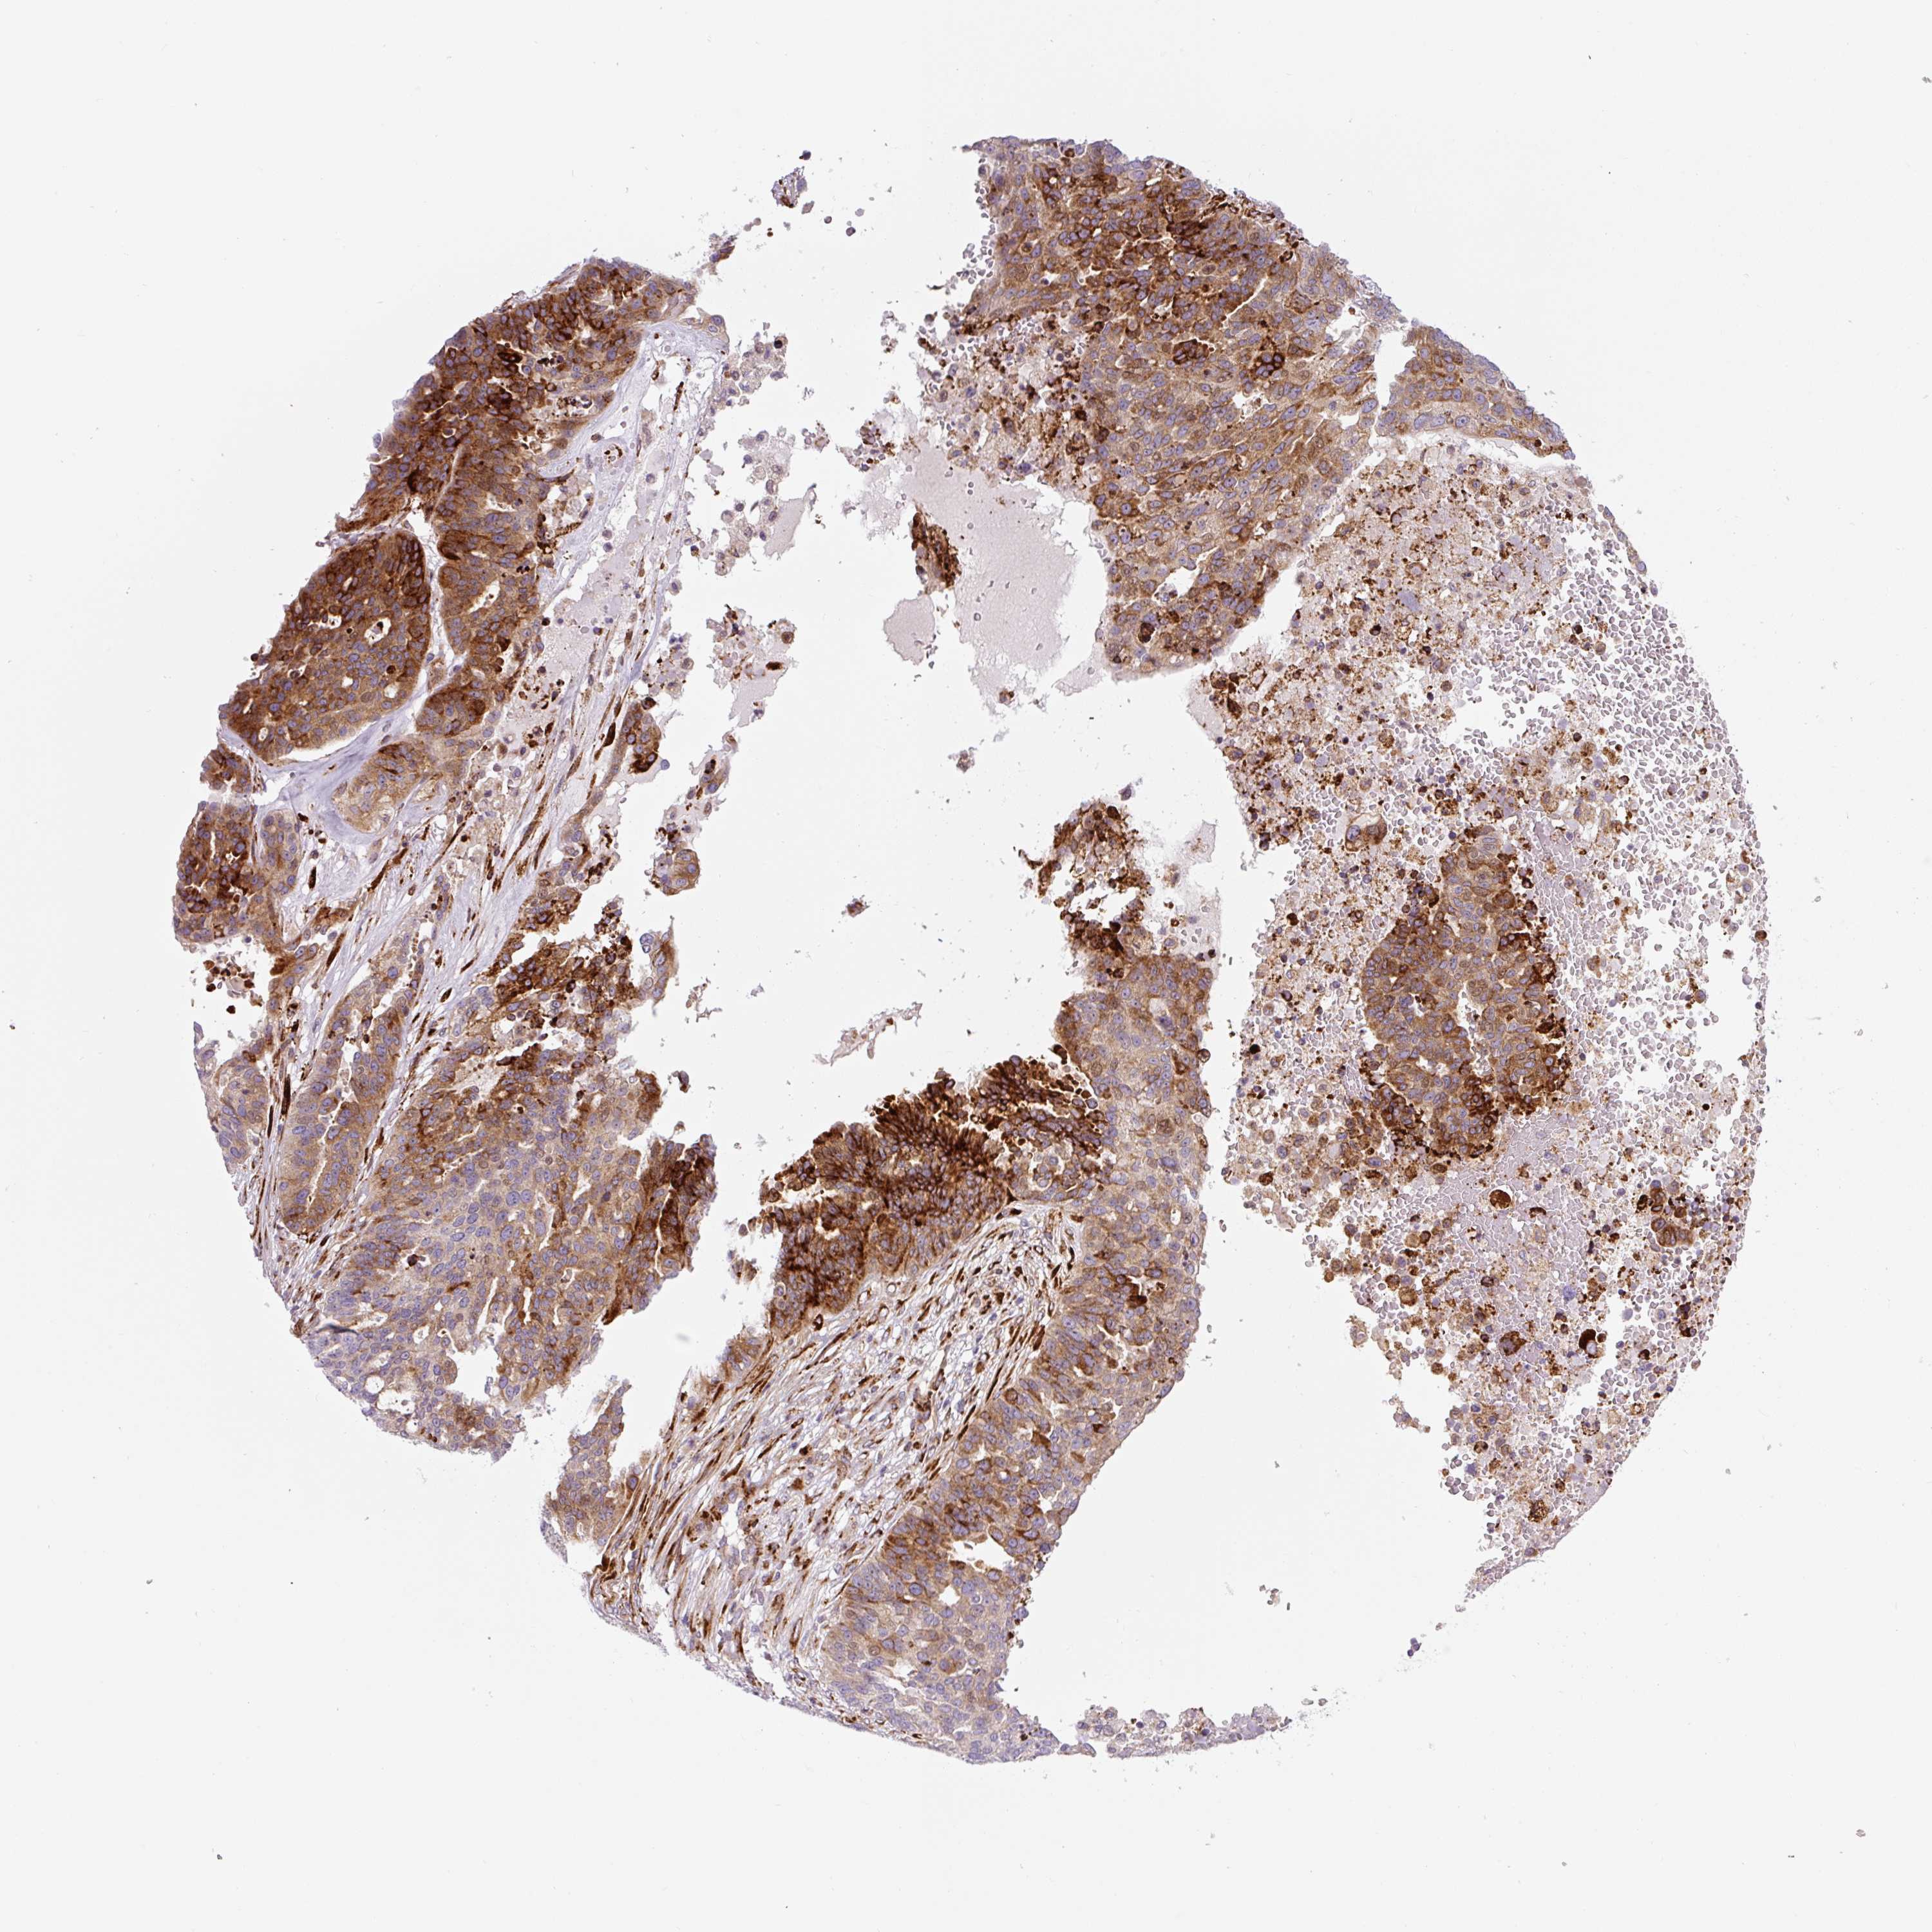

OVARIAN CANCER - Protein expressioni

A mouse-over function shows sample information and annotation data. Click on an image to view it in a full screen mode. Samples can be filtered based on level of antibody staining by selecting one or several of the following categories: high, medium, low and not detected. The assay and annotation is described here.

Note that samples used for immunohistochemistry by the Human Protein Atlas do not correspond to samples in the TCGA dataset.

Antibody stainingi

Antibody staining in the annotated cell types in the current human tissue is reported as not detected, low, medium, or high, based on conventional immunohistochemistry profiling in selected tissues. This score is based on the combination of the staining intensity and fraction of stained cells.

Each image is clickable and will lead to virtual microscopy that enables deeper exploration of all samples and also displays staining intensity scores, fraction scores and subcellular localization as well as patient and tissue information for each sample.

Antibody HPA054579

Staining

High

Medium

Low

Not detected

Intensity

Strong

Moderate

Weak

Negative

Quantity

>75%

75%-25%

<25%

None

Location

Nuclear

Cytoplasmic/membranous

Cytoplasmic/membranous,nuclear

Cystadenocarcinoma, serous, NOS

Carcinoma, endometroid

Cystadenocarcinoma, mucinous, NOS

Carcinoma, NOS